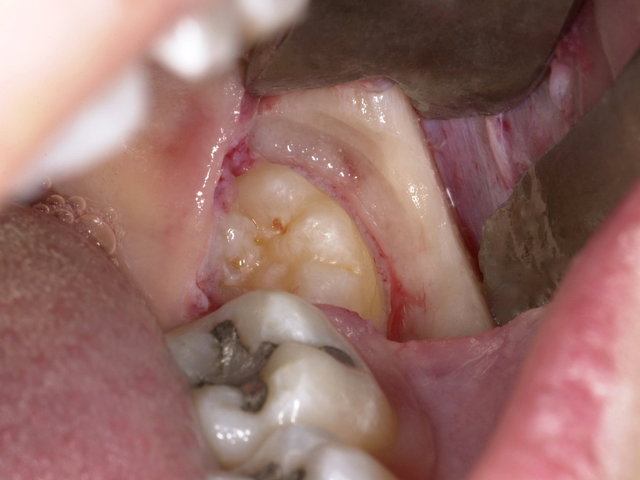

Operative Weisheitszahn-Entfernung ... ✓